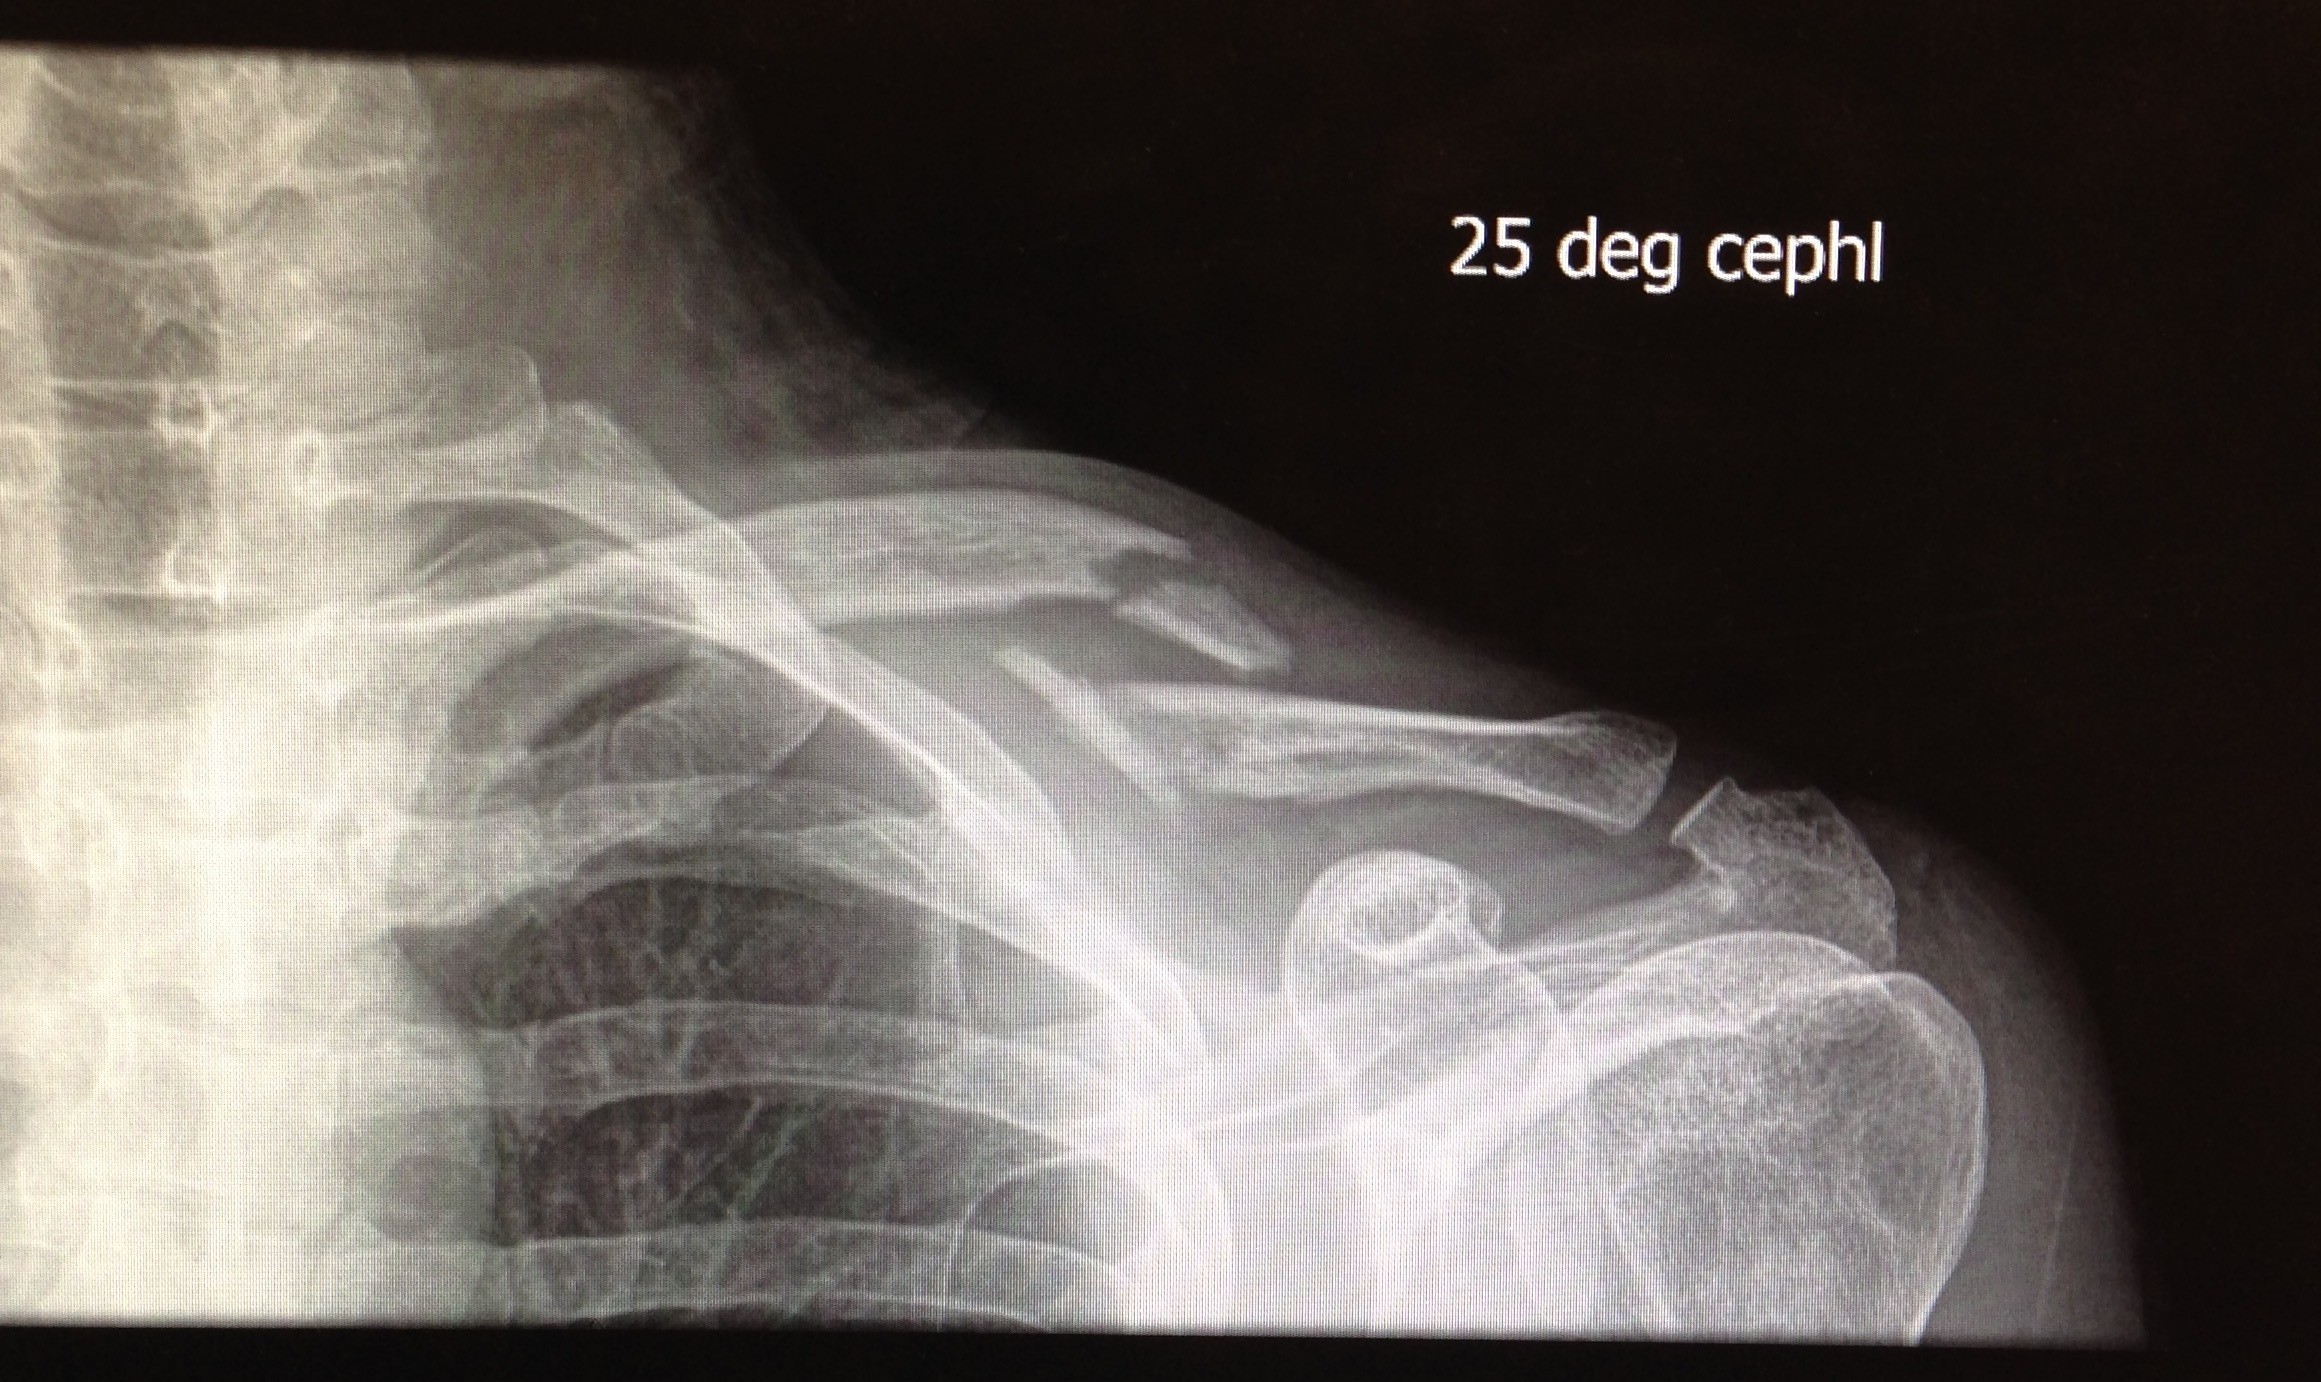

X-ray of my left collarbone, showing clean breaks in two places

While I was riding my bike home in South Waterfront, a driver opened his car door into the bike lane, knocking me off my bike. I broke my collarbone and damaged my bike (and other things). I got myself to the OHSU emergency room, which turned into a really pointless visit; the only results were: